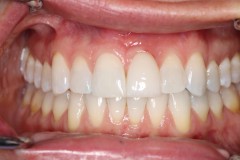

This young patient was self-conscious about the appearance of her short teeth and gummy smile. Through crown lengthening and tooth whitening procedures, we were able to create a beautiful, more mature smile.

Click on a thumbnail to view the before and after photos.